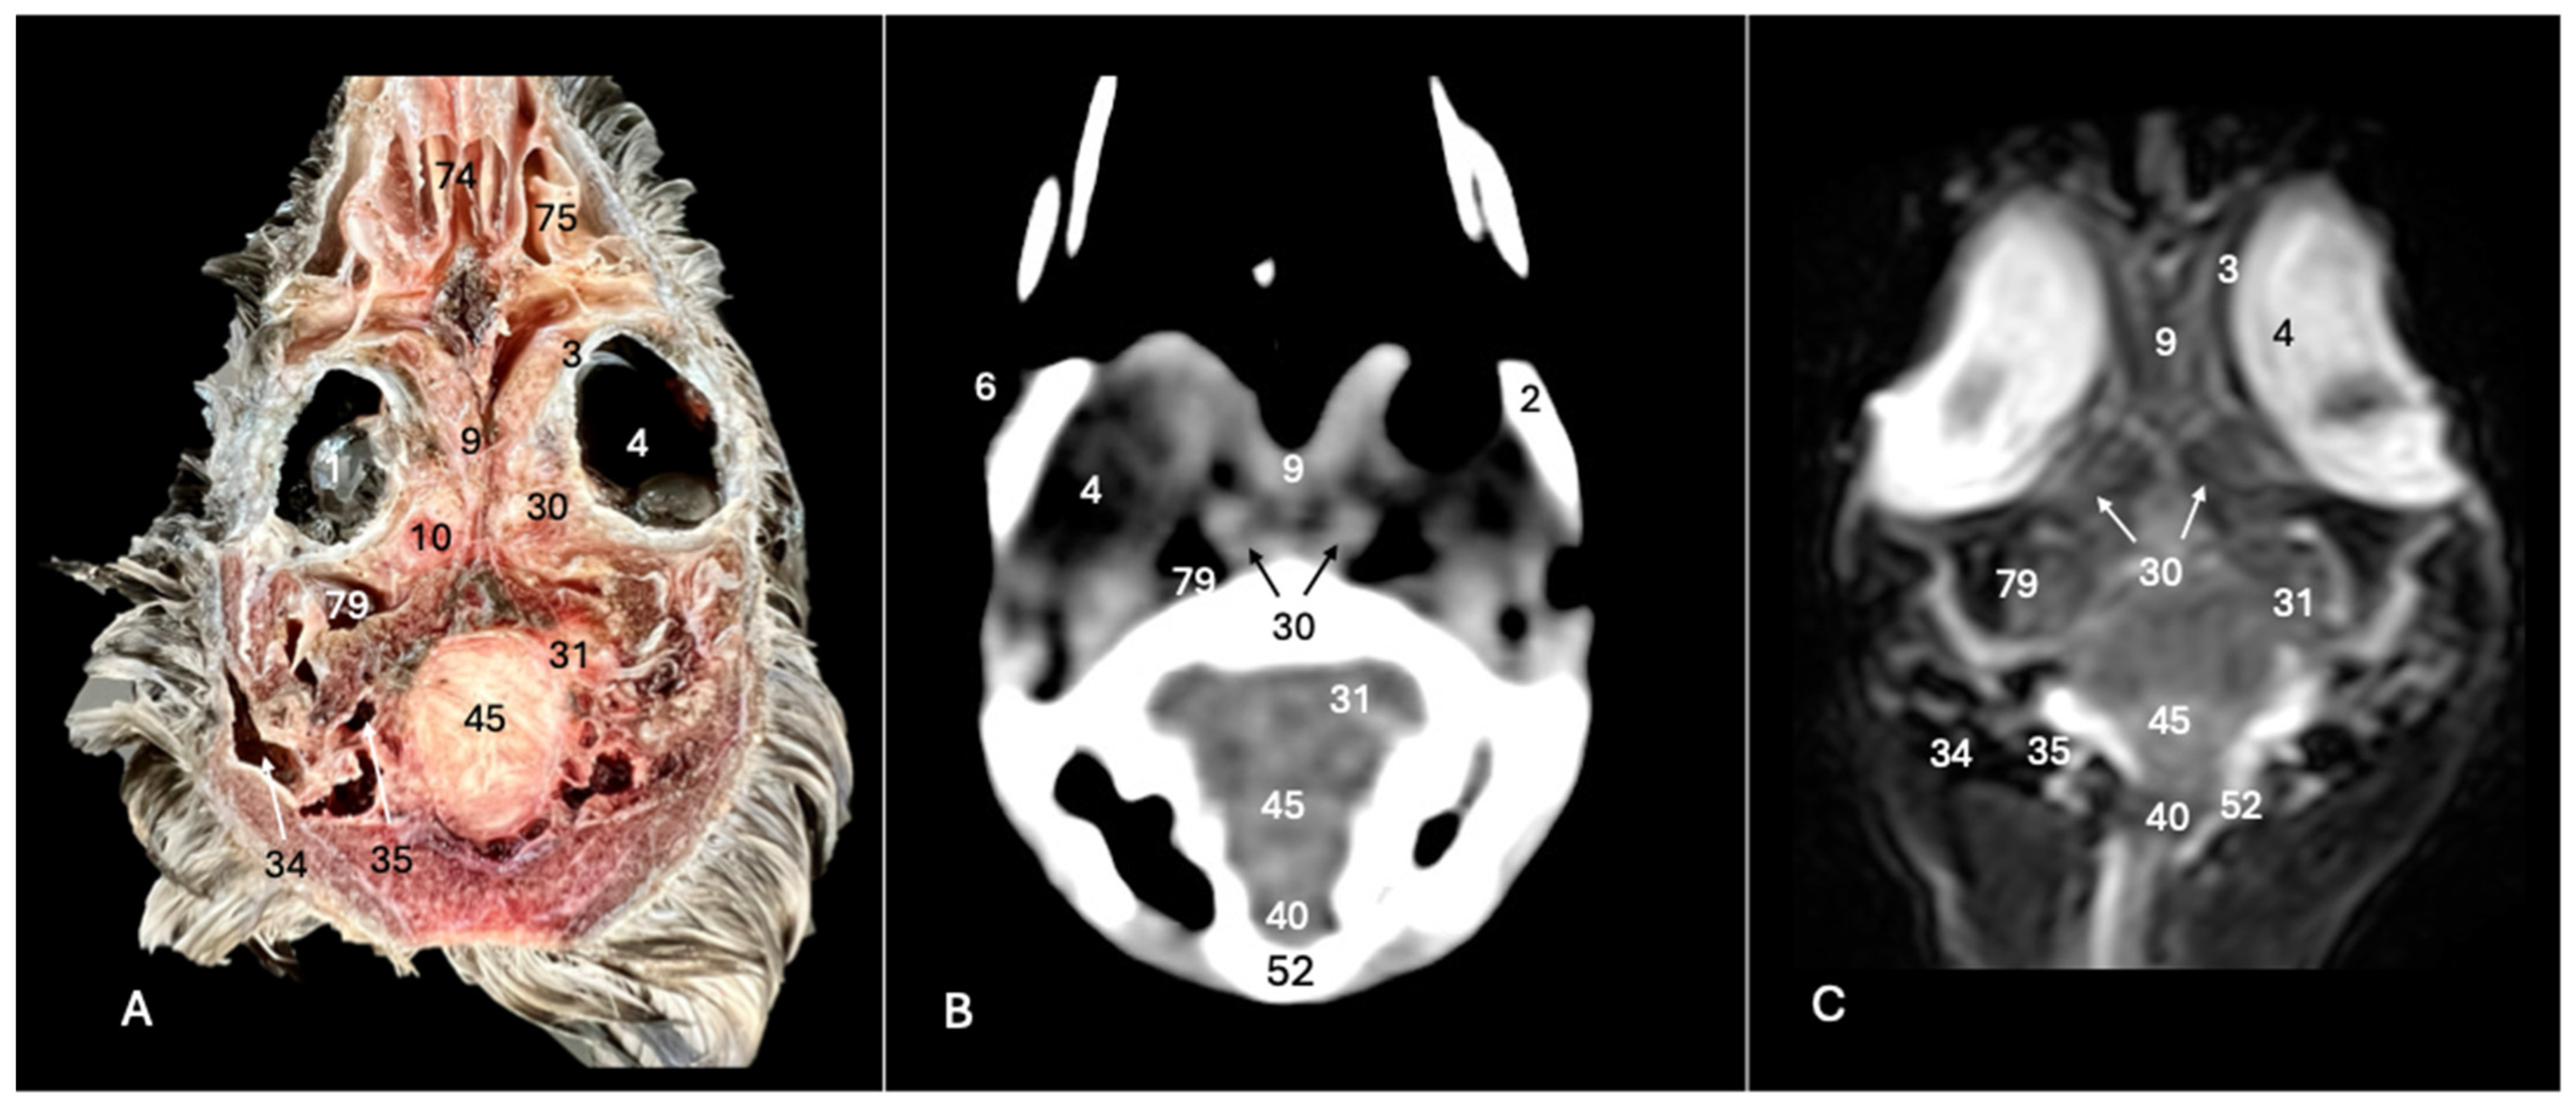

Figure 9. Anatomical cross-section (A), soft tissue CT window (B) and T2-weighted MR (C) dorsal images of the Cory’s shearwater head at the level of the optic nerve, corresponding to line VIII in Figure 1. 1: Lent cristali; 2: sclerotic ossification; 3: sclera; 4: camera vitrea bulbi; 6: camera anterior bulbi; 9: septum interorbitalis; 10: extraocular muscle; 30: optic nerve; 31: optical lobe; 34: external acoustic canal; 35: inner ear; 40: medulla oblongata; 45: cerebellum (body); 52: os supraoccipitali; 74: concha nasalis media; 75: concha nasalis caudalis; 79: pneumatization of the temporal bone.